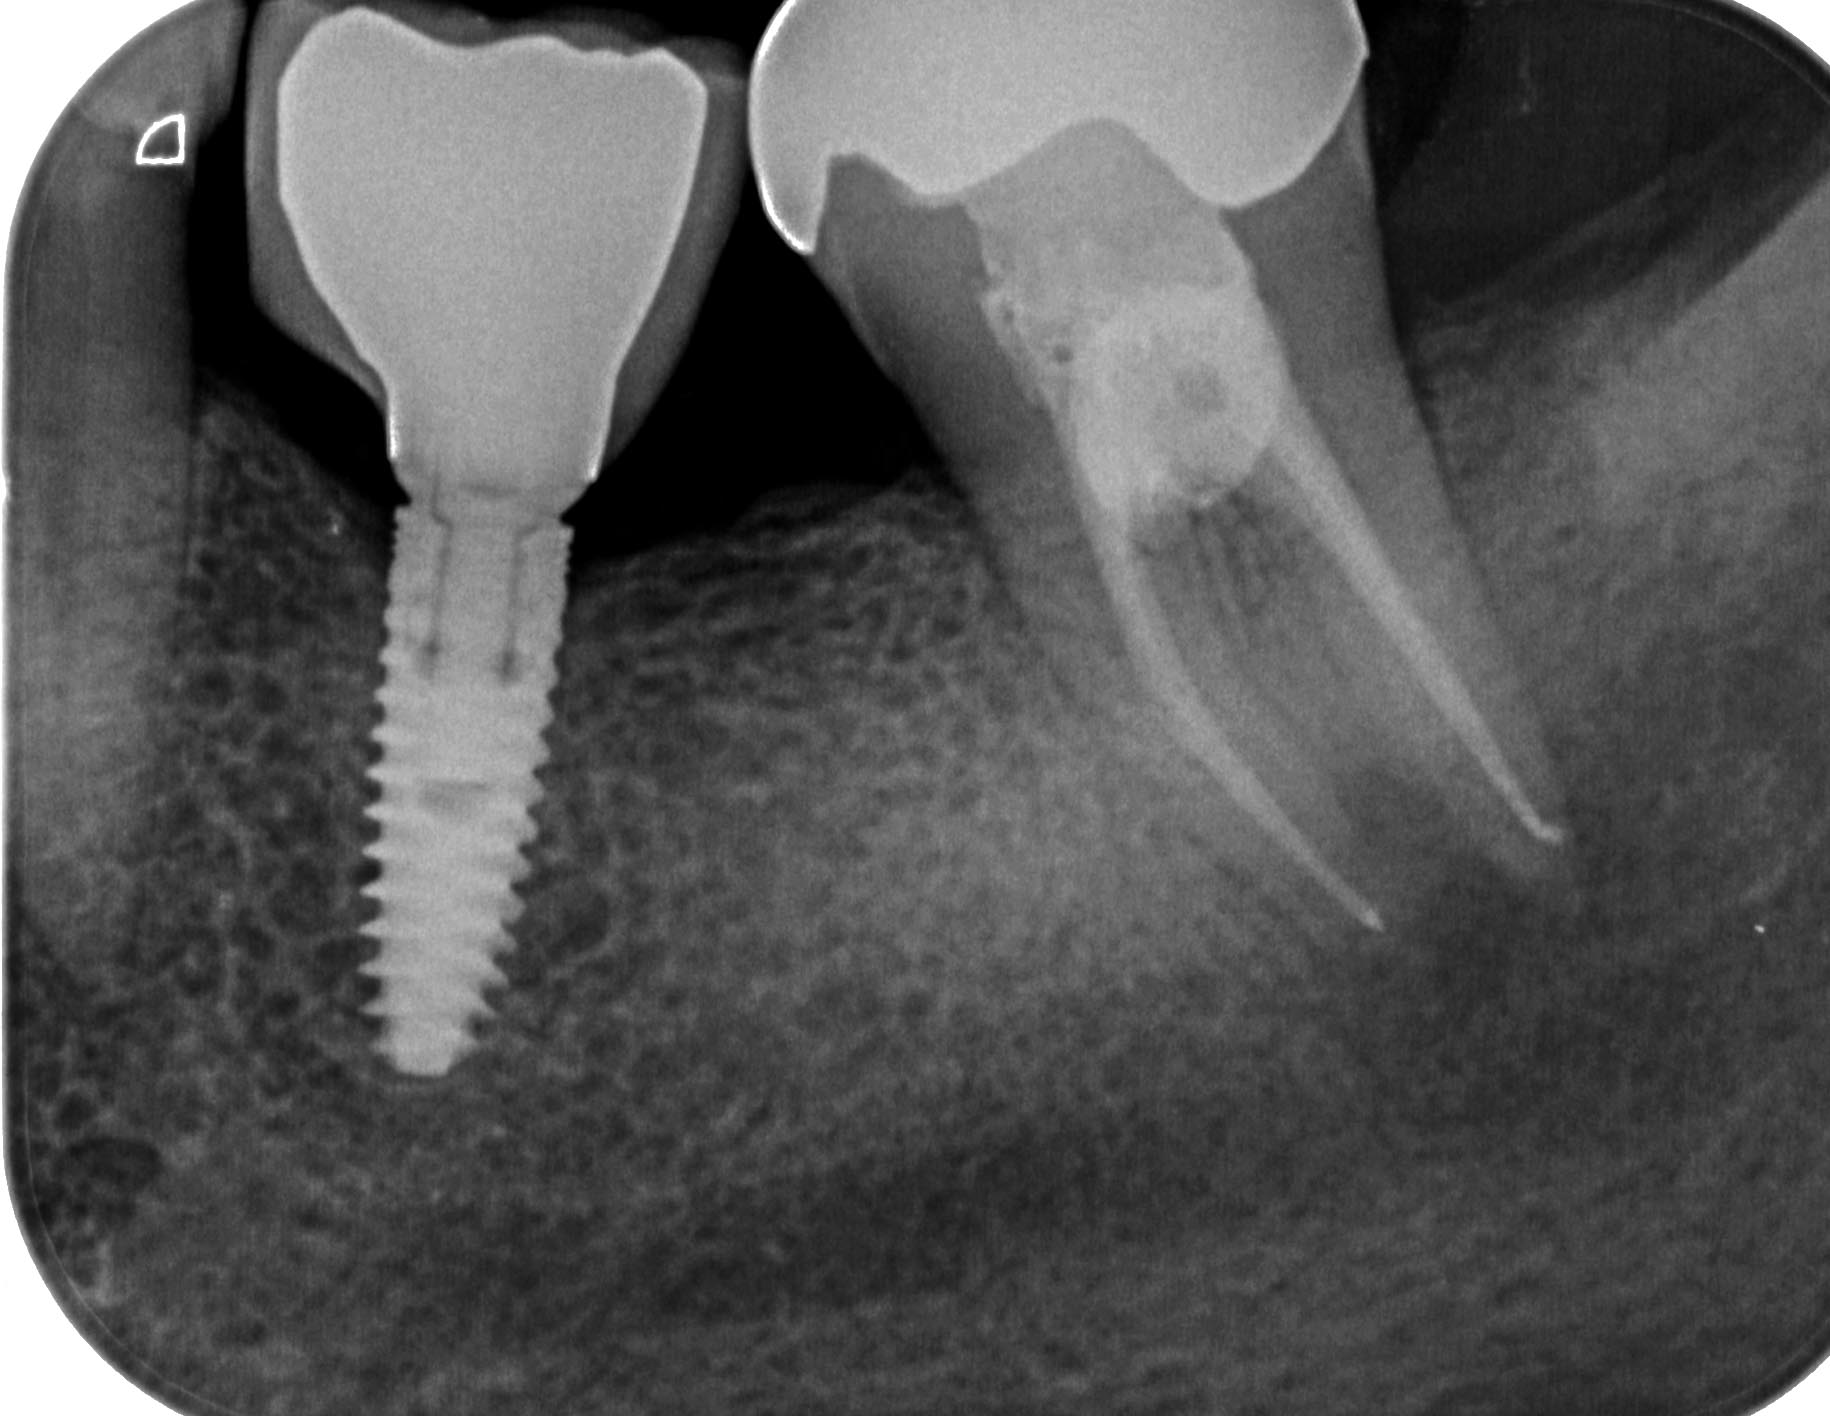

Distal-6 Veröffentlicht 16. Mai 2016 am 1830 × 1416 in Starker distaler Knocheneinbruch – Lohnt der Versuch eines Zahnerhaltes ? Zahn 37 WF Oktober 2014